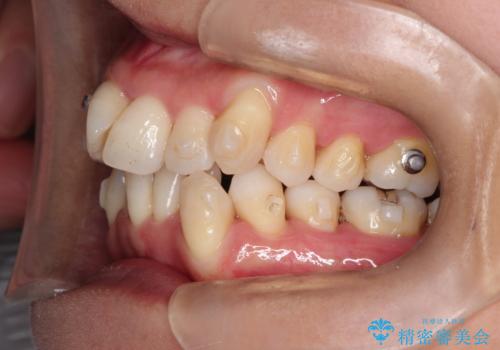

重度のガタガタのインビザラインによる非抜歯矯正

- 矯正装置

- インビザライン

- 上下の歯のガタガタを主訴に来院されました。

インビザラインで奥歯を後方に移動させるのと、歯と歯の間をわずかに削ることでスペースを作り、歯を並べる計画としました。